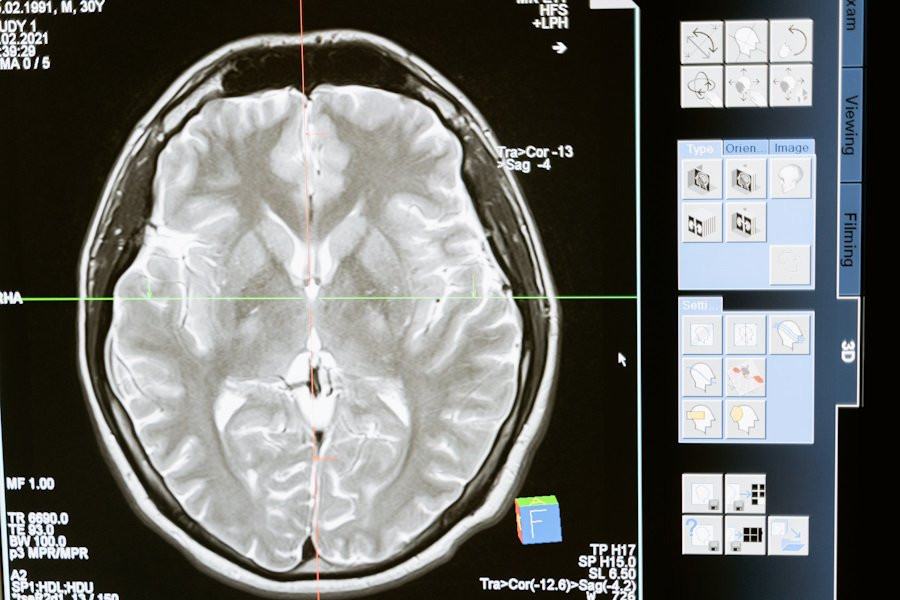

Фото из открытых источников

Исследования, опубликованные на портале eLife, предлагают новую перспективу на лечение деменции и психических расстройств, таких как шизофрения, аутизм и болезнь Альцгеймера. Ученые выявили изменения в кислотности мозга, что может стать ключом к разработке эффективных методов борьбы с этими состояниями.